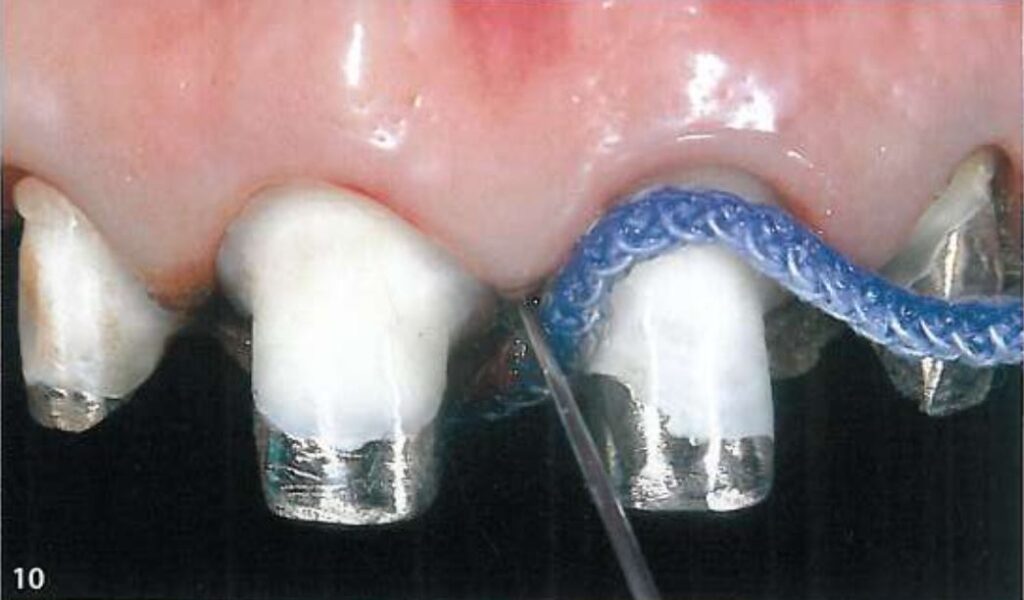

Khi chuẩn bị lấy dấu, phải thổi khô dịch và nước bọt xung quanh, sau đó gắp sợi chỉ ở trên ra (H10).

Sợi chỉ thứ 2 lớn hơn (Ultrapak #1) được đặt tiếp theo sau đó, không nhất thiết phải nằm hoàn toàn trong khe nướu (H10, 11).